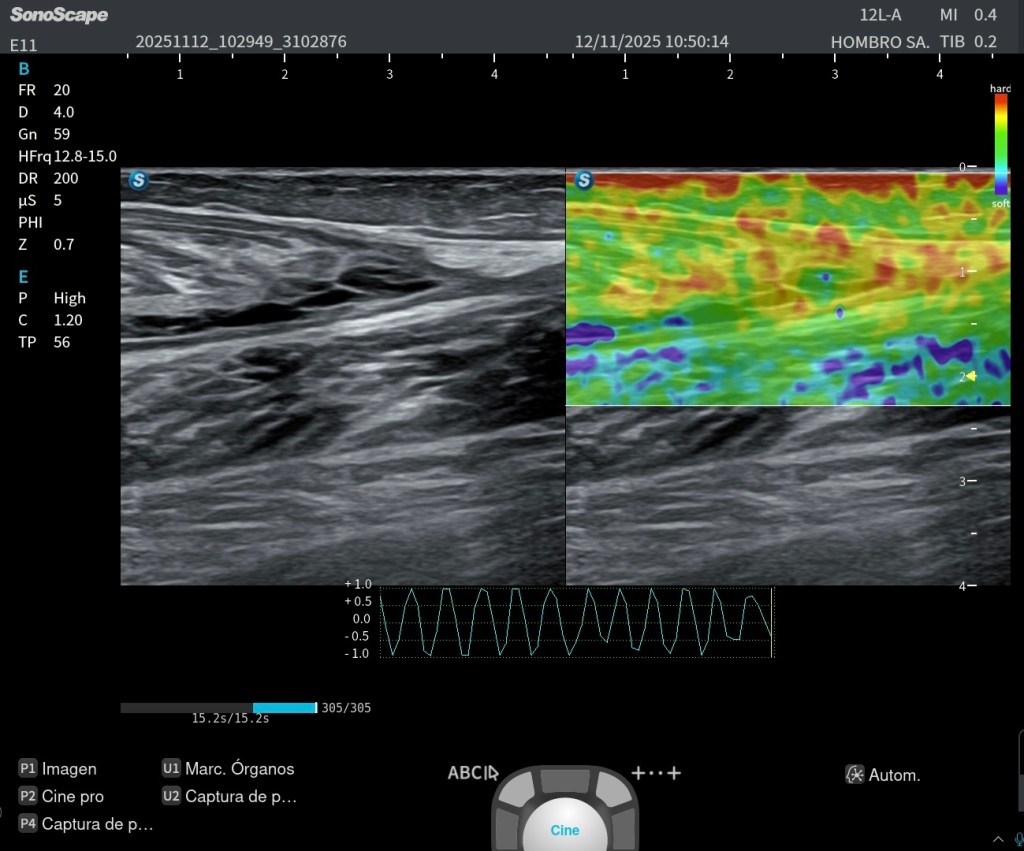

- En la imagen de elastografía de strain, se evidencia menor rigidez en la zona del hematoma, como es esperable, y mayor rigidez en las fibras retraídas, que se comportan de forma más fibrosa y densa en la fase de cicatrización.